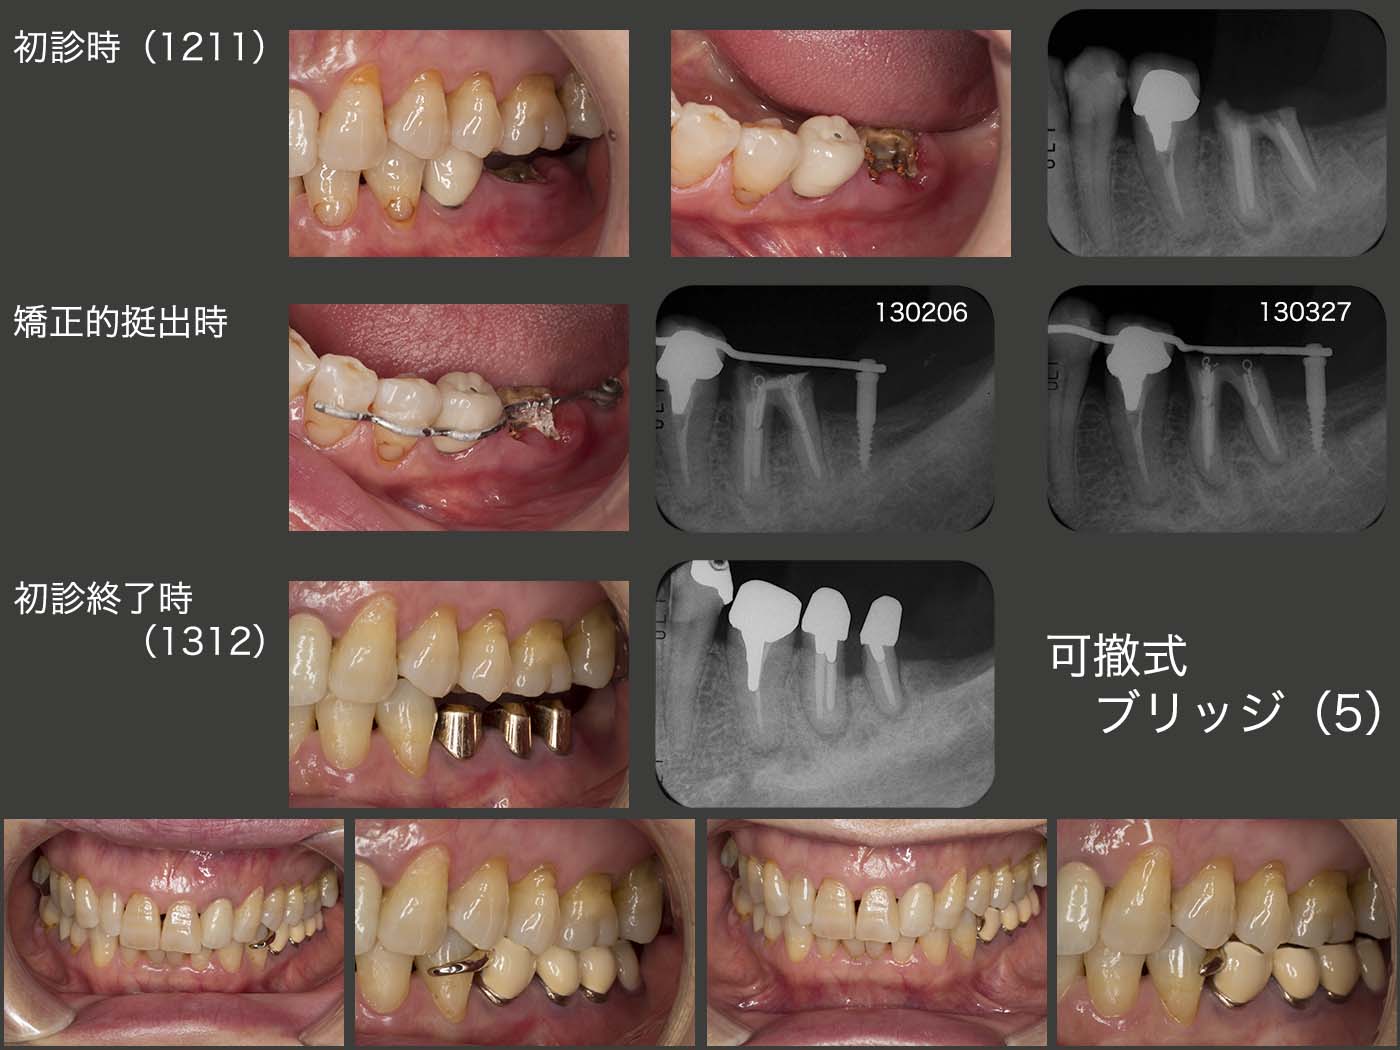

5.症例5

2012年11月初診,61歳女性.左下6を抜去し,インプラントを入れて欲しいが主訴.しかし,デンタルX線写真から十分保存が可能であり,自分の歯が何ものにも代えがたいことを説明した.しかし,このままでは歯肉縁上歯質がないため,冠の保持を得るために,まず矯正的挺出を行った.なお,遠心の固定源にミニインプラントを用いた.歯根を挻出し終わったところで,歯冠長延長術を行い,歯肉縁上歯質を確保した.左下6が分割されたことおよび左下7が欠如していることから,可撤式のブリッジ(コーヌス義歯)を選択した.

この時点で,患者さんの遠方への転居が決まっていたため,将来何かしらの理由で左下6を失った場合を考慮し,左下4にクラスプを付与した.しかし,審美的にどうしても受け入れられず,鉤端を切断せざるを得なかった.現時点においては,クラスプは転ばぬ先の杖であり,切断しても機能的にはほとんど影響を及ぼさない.将来,左下6を失うことがあった場合は,その時にまたクラスプを作り替えるか,どうしてもクラスプが審美的に嫌なら左下4を削去してコーヌス冠を装着してくださいと説明し,ご理解いただいた.

その後約7年(20年8月)が経つが,年2回の経過観察にもいらしていただいており,順調に推移している.